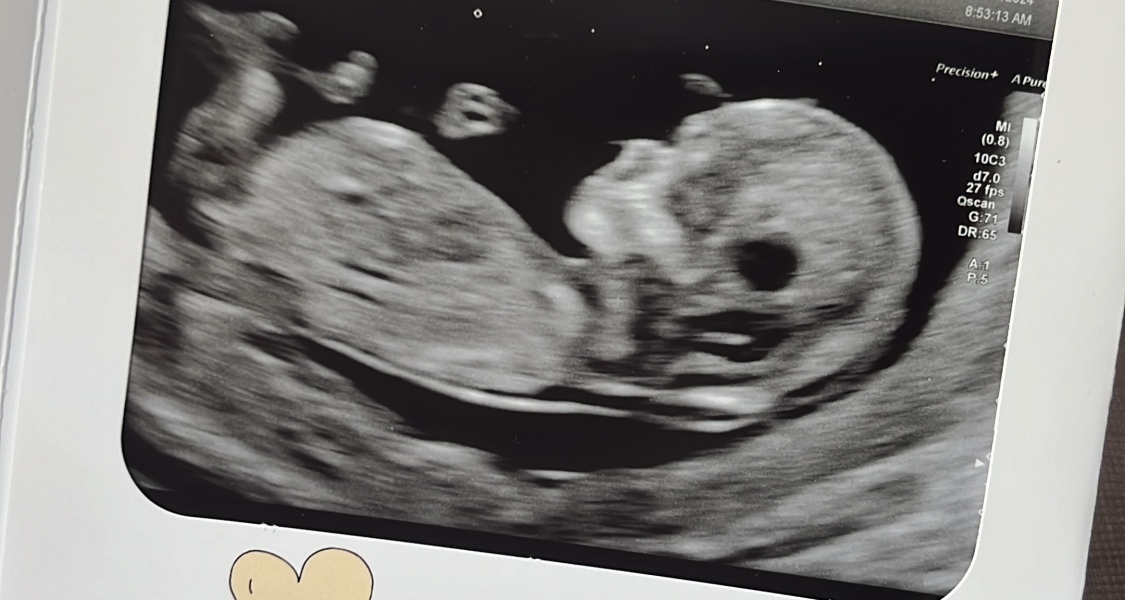

@ThisElatedMintDreamer The skull on your ultrasound looks like ours and ours turned out to be a boy!

My pics are sooo bad from the scan due to the little fidget showing off 😂 I've tried to compare to my son's 12 week scan and there are similarities so think we are having another boy.

Good morning! Hoping to join I am due 7th June! I had my scan and blood test on 29th still haven’t heard the results hoping to today xx this is my scan 12 weeks 6 days if anyone would like to guess I just have no clue! 🙈 xxxx